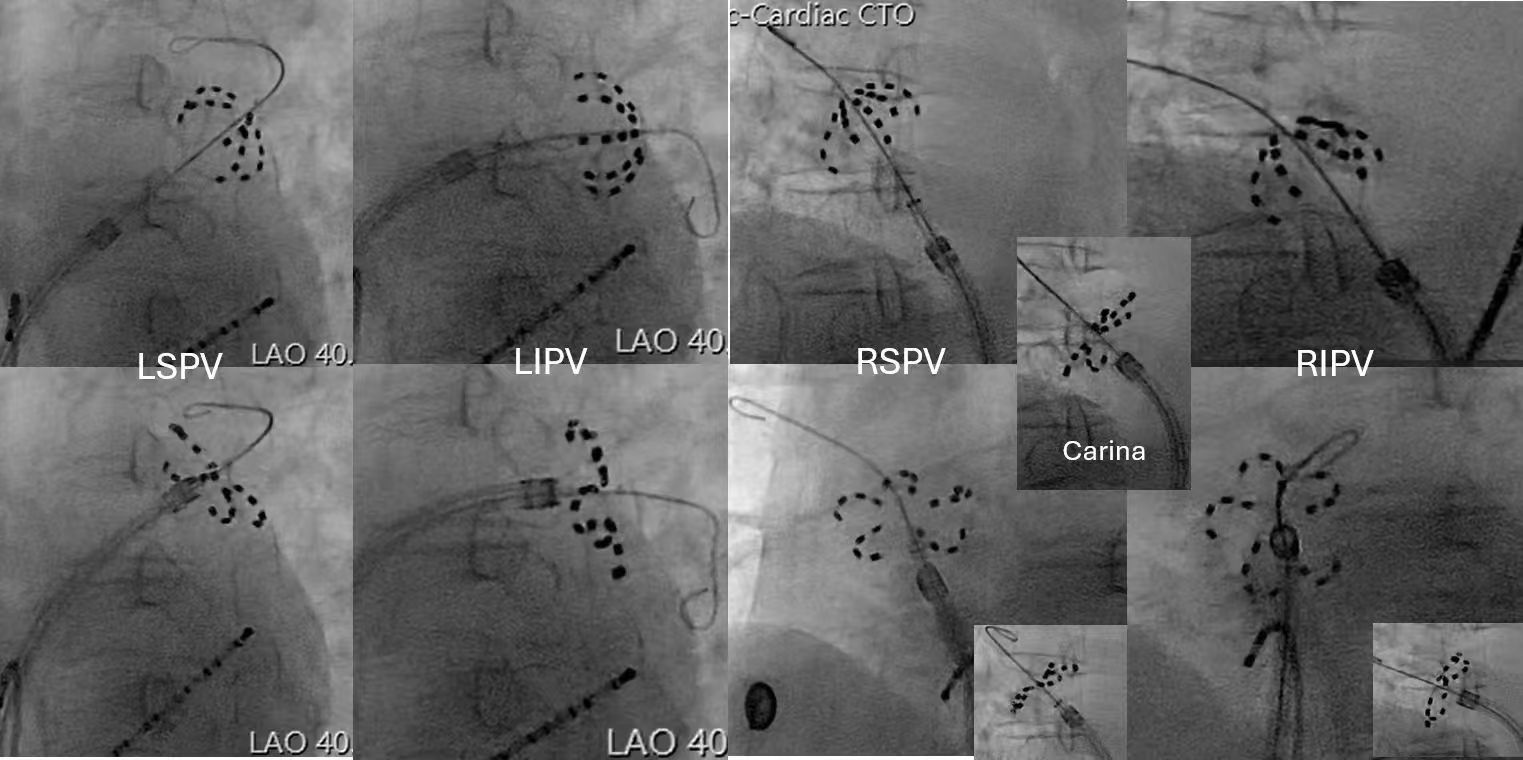

术中,杨桂棠主任团队应用我院刚刚投入使用的东北首台脉冲设备,凭借丰富的介入经验,精准操控,通过低能量、高频率的脉冲电场对肺静脉进行隔离,有效阻断房颤触发机制;随后,顺利完成左心耳封堵,消除血栓形成的隐患。整个手术过程流畅,术后患者生命体征平稳,房颤症状显著改善。这台手术的成功,标志着我院在东北地区心律失常治疗领域率先迈入“脉冲精准时代”。

脉冲电场消融术中